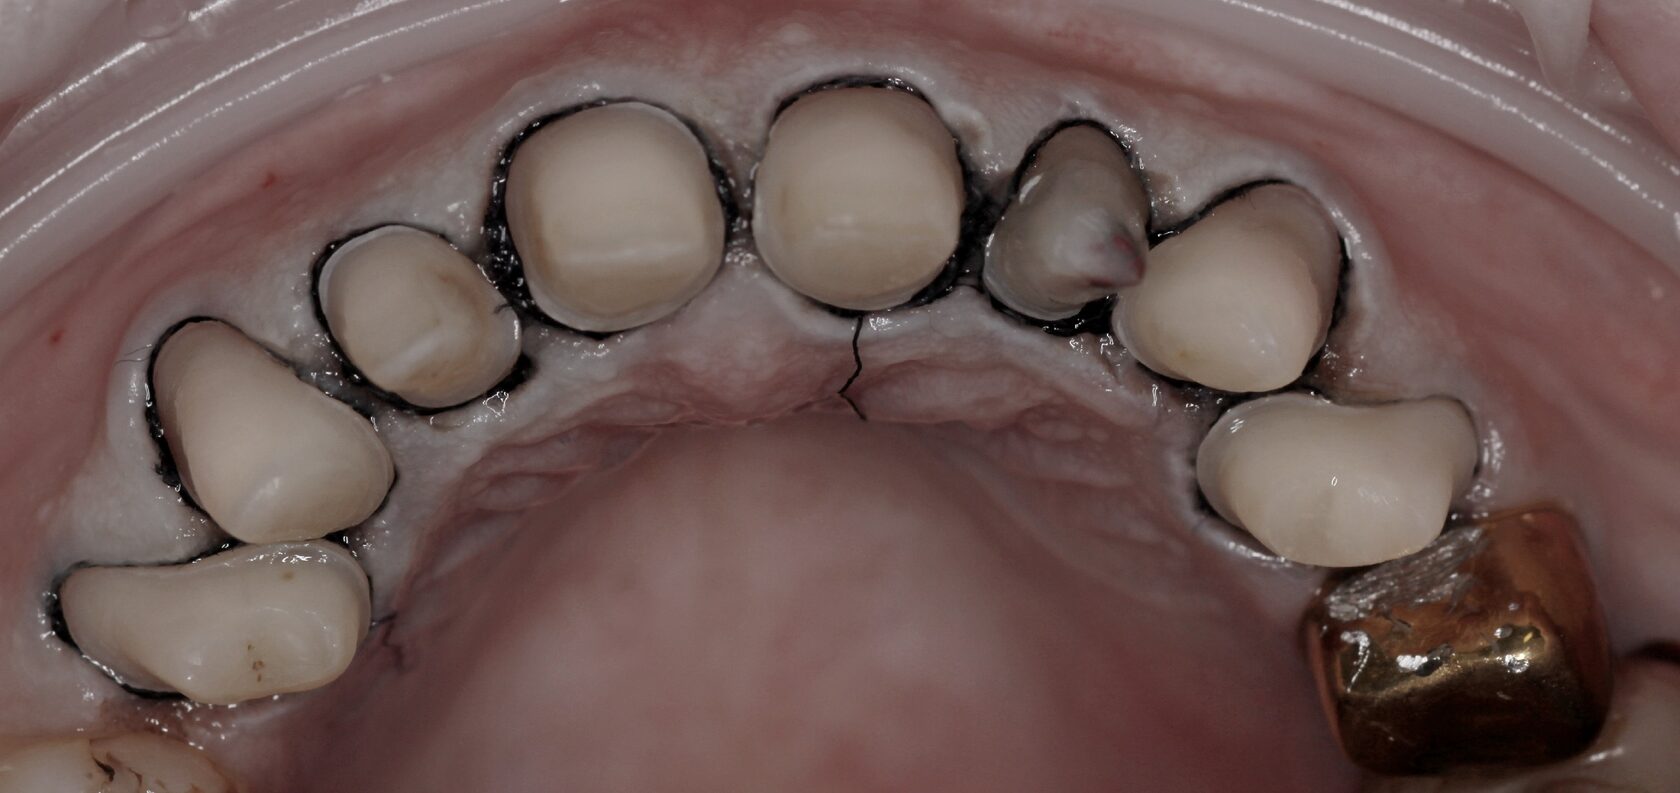

Пациентка С. обратилась с жалобами на щелчки в области наружного слухового прохода слева, дискомфорт при жевании, повышенный тонус жевательной мускулатуры, нарушение эстетического вида фронтальной группы зубов верхней челюсти, сколы композитного материала, желанием индивидуализировать свою улыбку.

Полная эстетическая реабилитация

В процессе диагностического исследования выявлено: наличие несостоятельных композитных реставраций зубов 1.3, 1.2, 1.1, 2.1, 2.2, 2.3, множественные сколы, дебондинг, рецидивирующий кариес. Патологическая генерализованная стираемость легкой степени, некомпенсированная форма, снижение межальвеолярной высоты. Асинхронность движения суставных головок нижней челюсти, сопровождающихся щелчком слева.

По результату планирования ортопедической реабилитации составлен предварительный план лечения:

1. Выполнения профессиональной гигиены полости рта

2. Изготовление временных эстетических ортопедических конструкций зубов 1.1, .1,2, 1.3, 2.1, 2.2, 2.3

3. Компенсация отсутствующего зуба 4.6 посредством дентальной имплантации.

4. Последовательное восстановление дефекта зубного ряда верхней челюсти безметалловыми конструкциями 1.7, 1.6, 1.5, 1.4, 2.7, 2.6, 2.5, 2.4

5. Восстановление дефектов зубного ряда нижней челюсти безметалловыми конструкциями 3.6 3.7, 4.6, 4.7

6. Изготовление безметалловых конструкций зубов 1.1, 1.2, 1.3 ,2.1 2.2 ,2.3

7. Изготовление оксид-циркониевых виниров зубов 3.3, 3.2, 3.1 4.1 .4.2 ,4.3

8. Изготовление эластичной каппы зубного ряда нижней челюсти, для лучшей адаптации в постреабилитационном периоде.

Использование поляризационного фильтра для оценки монохромности эстетических конструкций в зоне улыбки.